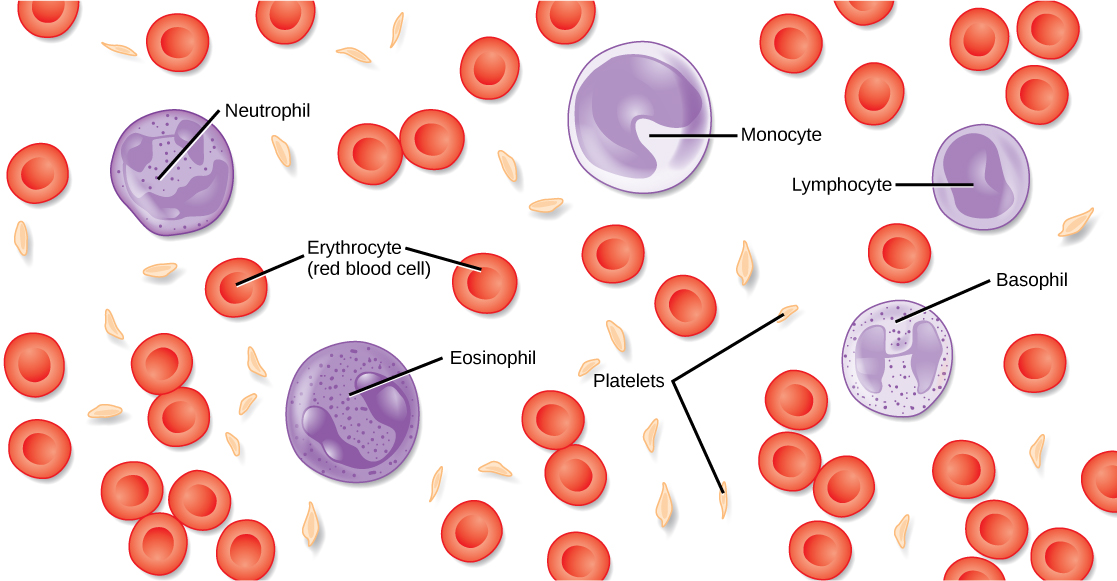

- Components of blood and their functions (Red blood cell, white blood cell, platelets and plasma (blood groups)